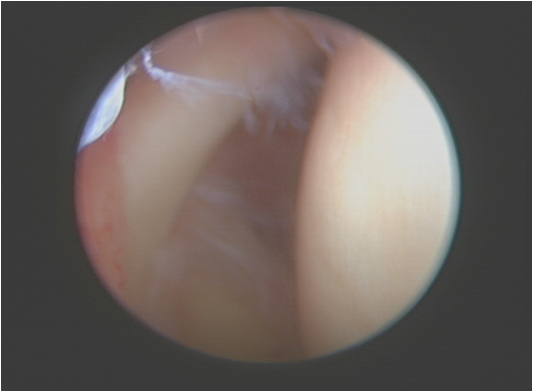

肩关节镜手术